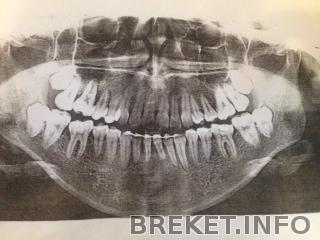

Сегодня с утра удалила ретинированный горизонтальный зуб мудрости (а точнее зубище)! Ровно два месяца я не могла решиться, придумывала себе разные причины и оттягивала этот неприятный момент! Перечитала весь интернет -кто как удаляет зубы, даже видео смотрела! лучше б я этого не делала! Я боялась даже представить себе операцию по его извлечению и думала только об этом)) Поэтому, если Вам надо удалять восьмерки - Ни в коем случае не читайте про это и уж точно не смотрите видео! Читать далее »